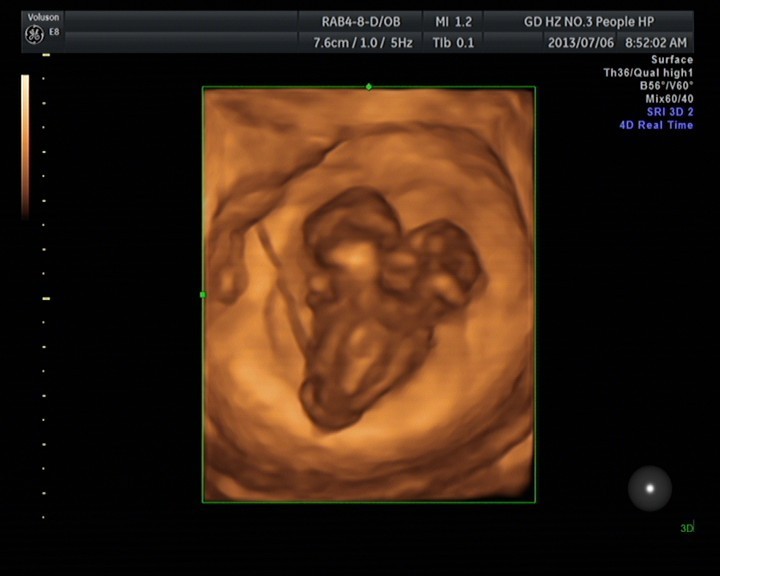

随着环境污染日益严重,随着各种地沟油的诞生,随着各样镉大米的泛滥……我们的健康越来越受到威胁,很多疾病也随之接踵而至,胎儿先天性疾病也越来越多见。7月6日,我院超声科王瑶医生在做胎儿产前NT筛查中发现一例孕约11周+的联体双胎。超声所见:增大的子宫内可见联体双胎儿回声,可见两个胎头不能分离,胸部及腹部融合,可见一个增大的心脏。

联体婴儿B超图像